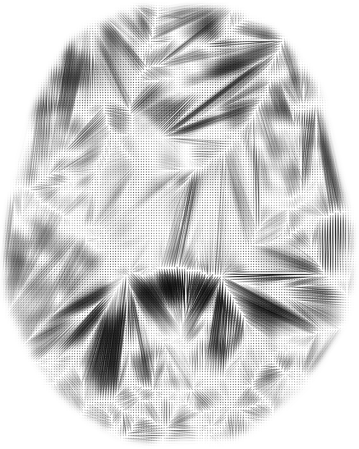

5 Application to Brain MR Images

An important building block for the analysis of brain MRI populations is the definition of a metric that measures how different two brain MRI are. A mathematically well motivated and popular approach for distance computations between brain images is based on large deformation diffeomorphic metric mappings (LDDMM (Miller et al., 2002)). Here we explore optimal transport distance as an alternative metric for comparing brain images.

To solve for the optimal transport map between two 3D brain images we extract for each image a point cloud from the intensity volumes. Each point represents a voxel as a point in 3-dimensional space, the location of the voxel. The mass of the point is equal to the intensity value of the voxel, normalized to sum to one over all points. For illustration, Figure 9 shows a single slice extracted from the original volumes and optimal transport maps between the two slices. This 2D problem resulted in point set of approximately points.

|

|

| (a) | (b) |

|

|

| (c) | (d) |